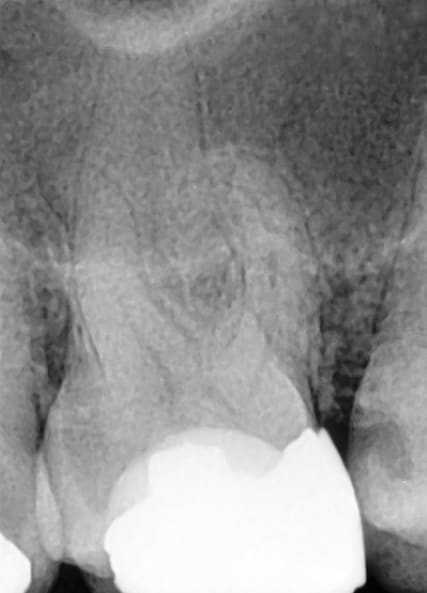

A 55-year-old patient presented for endodontic therapy with a diagnosis of irreversible pulpitis affecting a maxillary premolar. Radiographic assessment revealed partially calcified canal trajectories, suggesting chronic pulp inflammation (Figure 2). After conventional access and irrigation with Dual Rinse® (1.5% sodium hypochlorite [NaOCl] combined with a chelating agent compatible with NaOCl) (Medcem GmbH, medcem.eu), an EdgeOne Blaze Utopia R20 file was selected for canal preparation.